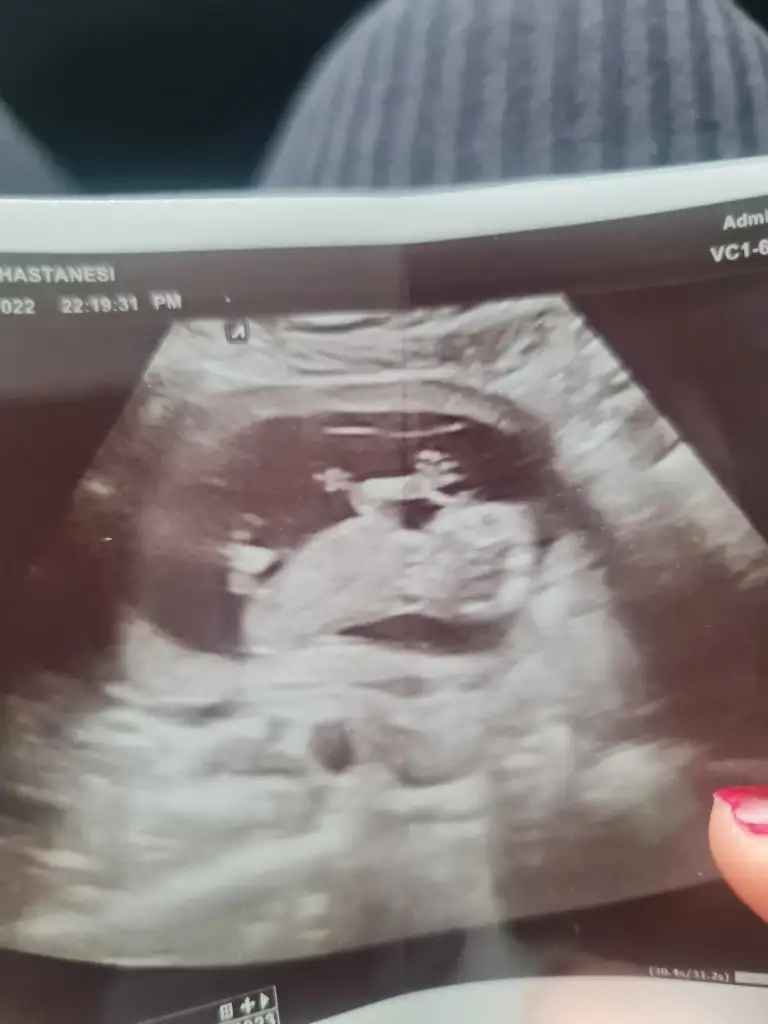

13 haftalıgız meraktan çatlıcam yakında doktor bi dahaki gelişinde söyleyebilirim dedi taa kurban bayramından sonra 🤭Lütfen bize de bir tahminde bulunur musunuz teşekkürler 🤗🤗

merhaba benim bebeğim ensen gittiğimde pek anlamdı doktor bacak arasından bunu verdi anlamadık sizce ne olablir

Doktor bişey demişmiydi sana?Ya benim 2 tane kızım olduğu için erkek bekliorum ama tabiki en doğrusunu Rabbim bilir:KK9:

Erkeğe benzetti doktor da canım ama net konuşmadı cuma günü öğrenirim diye düşünüyorum inşallah gönlünden geçtiği gibi erkek olur tabi insan hem kızı hem oğlu olsun ister benim için fark etmiyor ilk çocuğum bu ama çok merak ediyorum🤭🤭